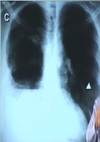

pneumotórax